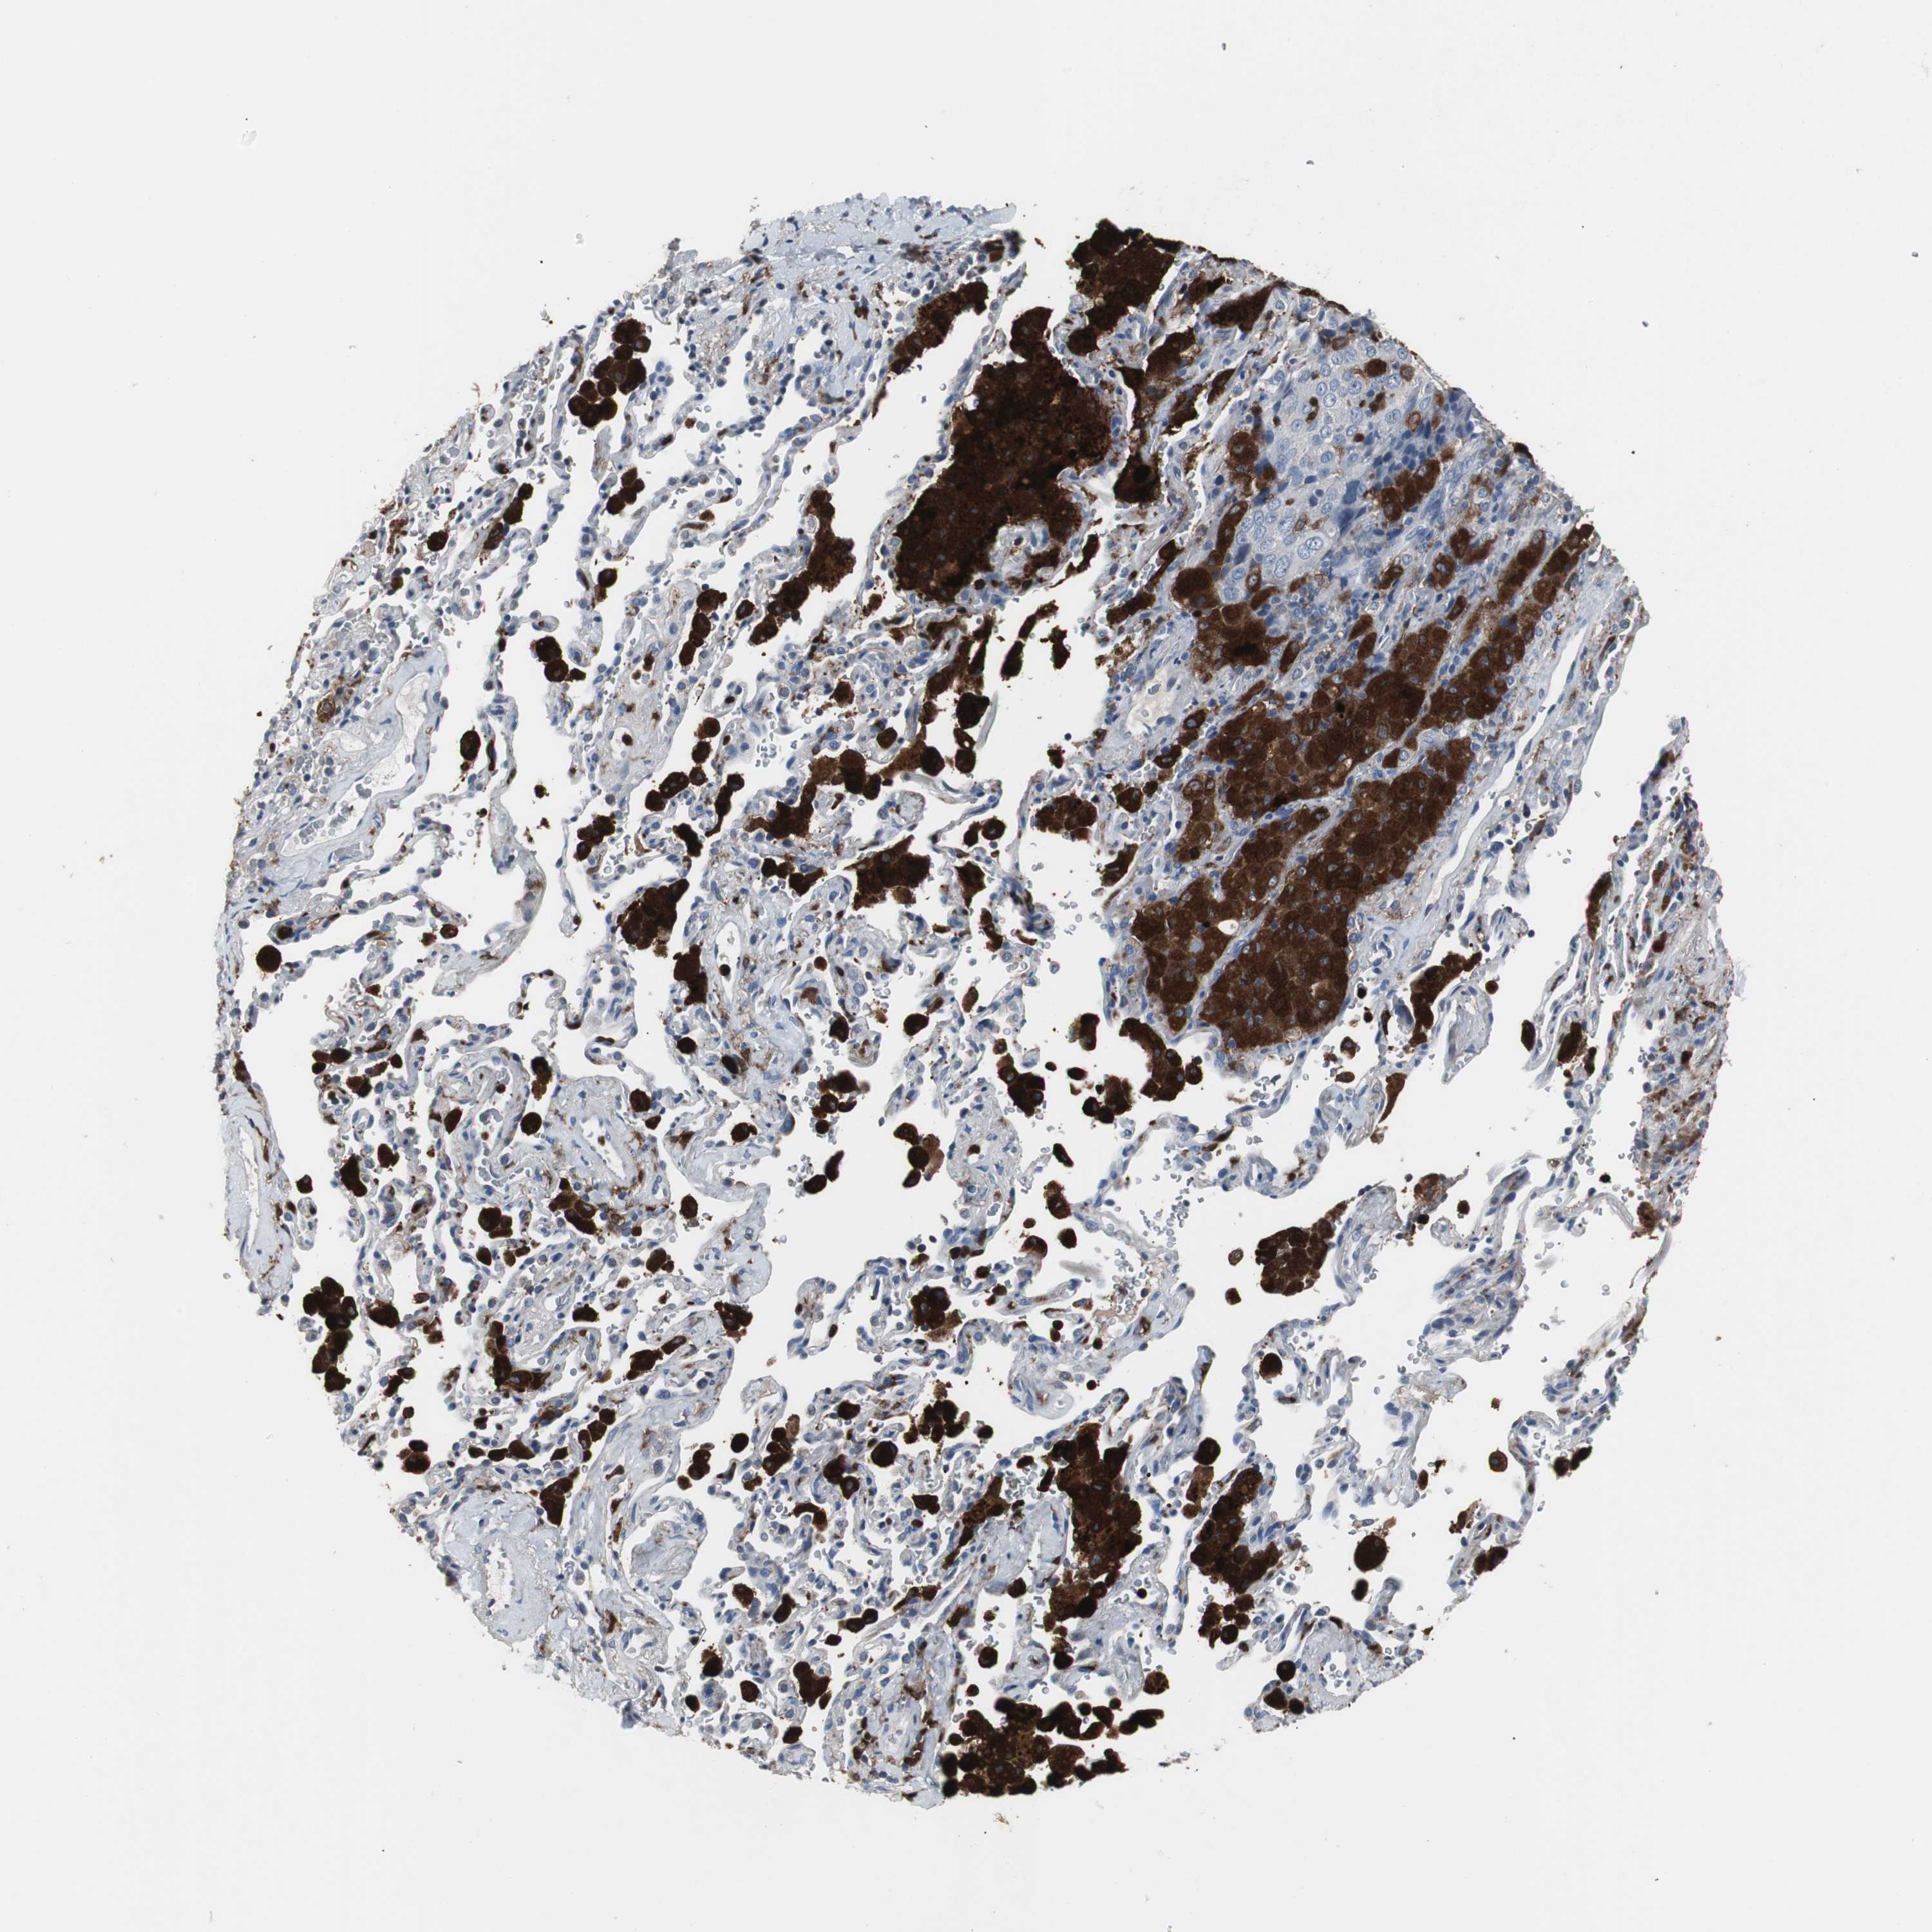

NCF2 is potential prognostic, high expression is unfavorable in Lung Adenocarcinoma (validation)

: 39.67

Average pTPM 62.0

Number of samples 105